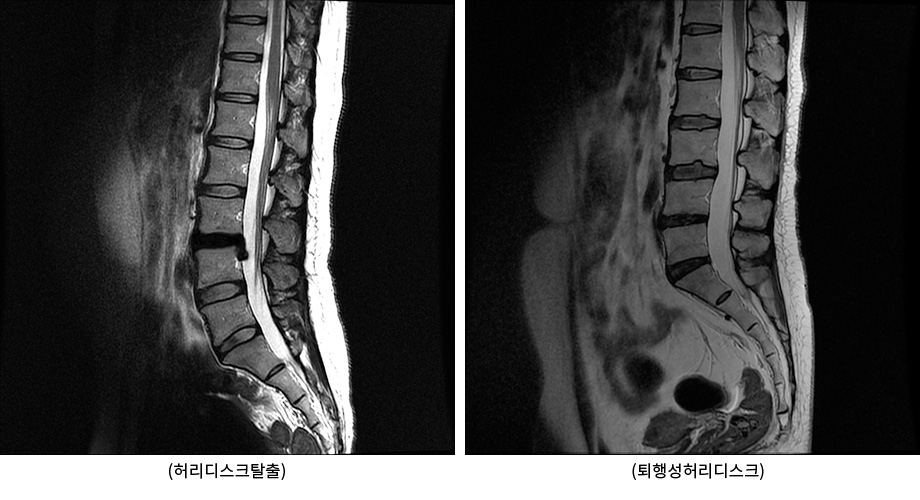

수많은 허리디스크 환자들이 허리 통증, 다리 통증을 줄이기 위해 여러 가지 허리디스크 운동을 찾아보고 시도하지만, 이 중 많은 사람들이 통증을 줄이는데 실패하거나 오히려 통증이 증가합니다. 이러한 실패의 이유에는 여러가지가 있는데, 가장 큰 이유 중 하나가 바로 허리디스크탈출과 퇴행성허리디스크를 구분하지 않기 때문입니다.

허리디스크탈출과 퇴행성허리디스크를 명확히 구분해야 한다.

우리나라에서는 이 둘을 구분하지 않고 모두 ‘허리디스크’라 부르기 때문에 사람들이 혼동하지만, 영어로는 허리디스크탈출과 퇴행성허리디스크를 명확히 구분하고 있습니다. 허리디스크란 사실 병명이 아니라 척추뼈와 척추뼈 사이에 있는 우리 몸의 일부분입니다. 다른 이름으로는 추간판이라고 부릅니다.

그럼 허리디스크탈출과 퇴행성허리디스크의 차이점은 무엇일까요? 허리디스크탈출은 디스크 외부를 보호하고 있는 섬유륜이 찢어져 수핵이 밖으로 밀려나와 다리로 가는 신경을 건드리면서 염증을 일으키고, 이에 따라 허리 통증과 극심한 다리 통증을 유발하는 급성기 상태를 말합니다. 이에 반해 퇴행성허리디스크는 허리디스크 탈출 후 급성기를 지나 디스크 손상이 복구되면서 어느 정도 안정화된 상태 혹은 허리디스크탈출 없이 나이가 들면서 허리 디스크의 퇴행이 진행된 상태를 의미합니다. 이런 두 질환의 차이로 인해 운동법, 관리법, 치료법도 완전히 달라지게 됩니다. 따라서 허리디스크탈출과 퇴행성허리디스크는 꼭 구별해주어야 합니다.